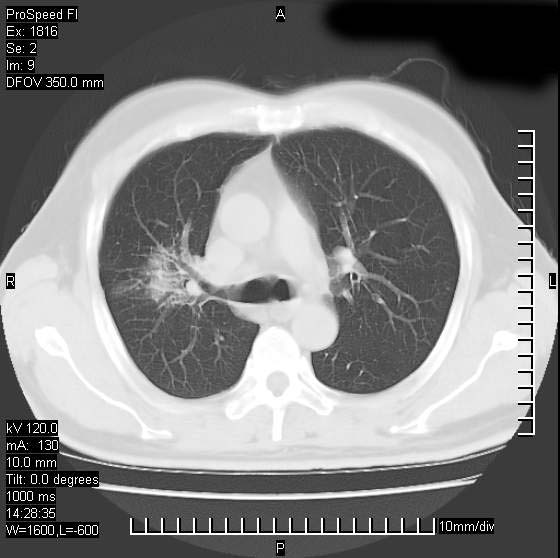

男性,50 ,肺结核9年,咳嗽,胸痛一周。右上肺见一厚壁空洞,周边有点样钙化,胸膜牵拉,洞壁较光整。诊断结核性空洞。有癌性的可能吗? 余肺野无异常,没有上传。

洞壁较厚内壁比较光整,两个病灶有关联性,纵隔淋巴结不大,考虑结核性空洞。

部分层面见空洞为近似新月形,洞壁内缘尚规整且近肺门侧,周围见索条影、卫星灶,结合病史,首先考虑肺tb可能大。

右肺上叶为两个病灶,前面为陈旧型结核灶,其后方病灶像肺脓肿

9年的结核应该呈现多形态病灶,该病例只能见到少许纤维索条影,似乎与结核的演变不太相符。空洞内壁不光整,外侧伴有胸膜粘连,考虑癌性空洞可能性大,期待结果。